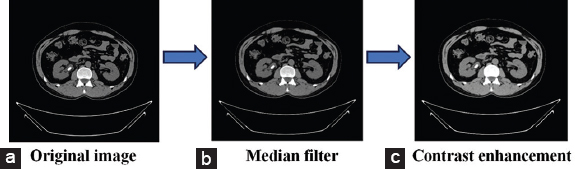

The images underwent a sequence of pre-processing procedures aimed at enhancing the input image’s quality, ultimately resulting in heightened accuracy for kidney stone identification. These pre-processing steps encompassed the conversion of the images to grayscale, preserving a spectrum of gray shades. Subsequently, a median filter was applied to reduce noise, and contrast enhancements were employed to enhance the visibility of objects within the image. Fig. 3 illustrates the results of this phase, particularly for a kidney with a stone.

thumblarge

Fig. 3. (a-c) The outcomes of the pre-processing phase.